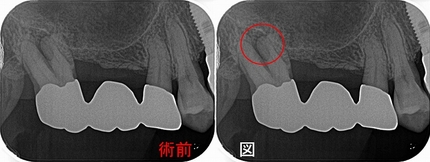

歯からくる副鼻腔炎で抜歯!?

患者さんは50代女性

2ヵ月前に歯茎が腫れその後フィステルが出てきた。

副鼻腔炎の症状もあり、近医では抜歯した方がいいと言われた。

現在、副鼻腔の方も詰まり変な臭いを感じる、歯は咬むと鈍痛、寝不足の際に違和感を感じる。

2026 EEdental ATI (1).jpg

近心頬側根に大きな根尖病変が見られます。

患者さんには歯の中の細菌感染が原因になっている可能性が高いので

まずは根管治療を行い⇒様子見 治らなければ外科的歯内療法を行い歯を残しましょうと説明

治療1回目

大きな根尖病変のあるMB根 MBの他にMB2が出てくるが途中で合流するパターン

全ての人工物を外し、隠れた神経管を探し徹底的に消毒

治療2回目

患者さんは術前時より鼻の臭いも取れ、鼻水も少なくなってきたとのこと

根管充填

2026 EEdental ATI (2).jpg

4根 ガッタパーチャーを使用

ここから経過観察

術後7ヵ月

2026 EEdental ATI (3).jpg

現在耳鼻科に通院中とのこと、

レントゲンでは根尖病変は小さくなってきているように見えます。

術後 1年3ヵ月

2026 EEdental ATI (4).jpg

耳鼻科にも現在通院中だが落ち着いてきている。

レントゲンでは病変の大きさは半分ぐらいになってきています。

先日、仮歯が割れてしまったとのことで、本歯を作らせてもらいました。

2026 EEdental ATI (5).jpg

クラウンSet後、根尖病変は殆ど無くなっています。

今回のケース結果的に、歯科と耳鼻科の複合要素でした。

ただ、個人的には発生の原因は歯だったのではないかなと思います。

細菌感染に配慮しない根管治療(神経の治療)を受けると2本に1本は膿んできてしまい、

奥歯だと副鼻腔に炎症が移行して鼻まで問題を起こすことがあります。

なるべく根管治療は細菌感染に対する配慮をしながら治療を受けられた方がいいと思います。